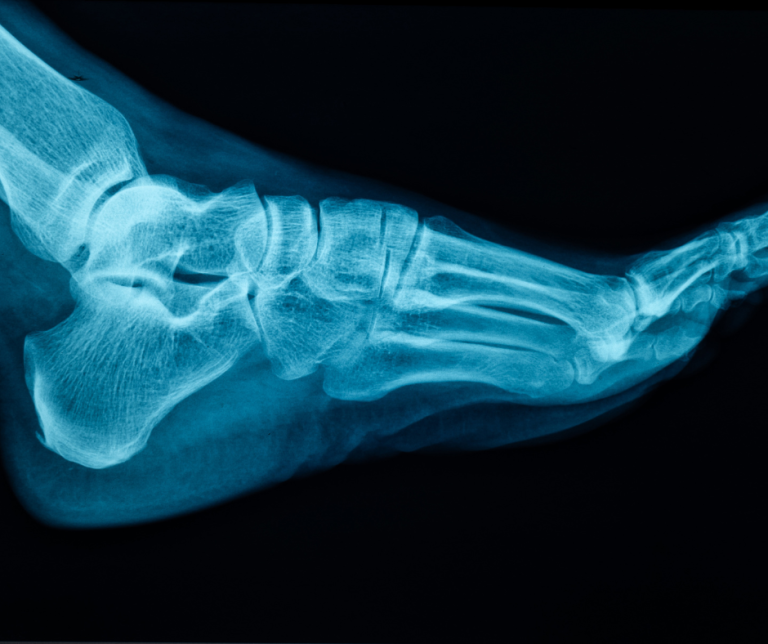

Unexplained Foot Pain? Advanced Diagnostics = Answers!

Are you experiencing foot pain, numbness, or swelling without a clear reason? The first step toward effective treatment is an accurate diagnosis.

Foot and ankle pain after an injury is common, but how do you know if it’s “just” a sprain or something more serious, like a fracture? Ignoring a broken bone can lead to long-term problems like chronic pain, arthritis, and difficulty walking. At Fulshear Foot and Ankle, we know it can be hard to tell…

Plantar fasciitis is a very common cause of heel pain, affecting millions. It involves inflammation of the plantar fascia, a thick band of tissue that runs along the bottom of your foot from heel to toe. But how do you know if you have it? Below, Fulshear Foot & Ankle has put together a guide…